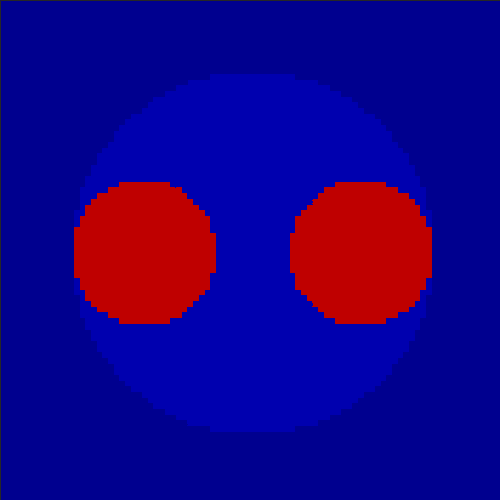

In order to test the behaviour of the proposed method in a more realistic, random-based test case, we performed a Monte Carlo simulation for dynamic SPECT imaging. First, we created a simple image phantom consisting of an outer and two inner circles which represents the structure of the region of interest (see figure 8(a)). Within those regions we assumed concentration curves over a time period of 90 time steps as displayed in figure 8(b). Based on the tracer intensity in an image frame at each time step, we created a variable number of random decay events (where the number is proportional to the average concentration in one pixel in the whole image frame per time step) with a probability proportional to the concentration in every subregion. They are detected by a virtual double head gamma camera rotating around the patient by 46 degrees per time step, which consists of 374 detector bins. Every simulated decay event is projected onto the scanner and counted by the corresponding detector bin.